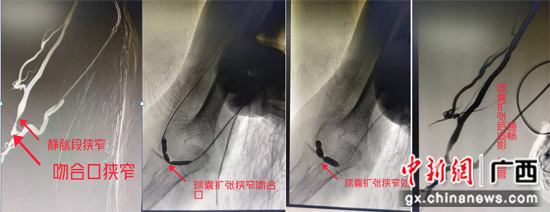

上图造影可见自体消息脉吻合口处明明狭窄、静脉段狭窄明明,球囊依次扩张吻合口狭窄处及静脉段狭窄处,再次造影可见狭窄明明改进。南溪山医院供图 据自治区南溪山医院主任胡长付先容,今朝自体消息脉内瘘(AVF)在该规模已经十分成熟,球囊将血管撑开后即可取出,不会滞留患者体内,术后患者立即就可以举办透析治疗,是急需透析而又血管狭窄的患者的最优选择。 据悉,广西壮族自治区南溪山医院血管外科连系肾病内科团队为血液通路透析患者精准、个别化的治疗,快速为患者清除血管狭窄及闭塞,小小球囊就能还血液透析患者一条通畅的“生命线”。 |